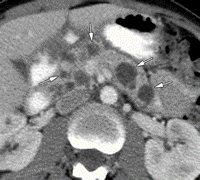

- Kontrastlı KT və ya MRT standart müayinədir, şişi və yayılma dərəcəsini müəyyənləşdirilməsində önəmlidir.

- Görüntüləmdə: erkən arterial fazada contrast tutan və venoz fazada yuyulan, MRT-də hipointens, ətraf toxumalara invaziv, böyüməyə meylli, baş nahiyyəsində yerləşərək xoledoxu və pankreatik axacağı genişləndirən (“iki axacaq simptomu”) törəmə